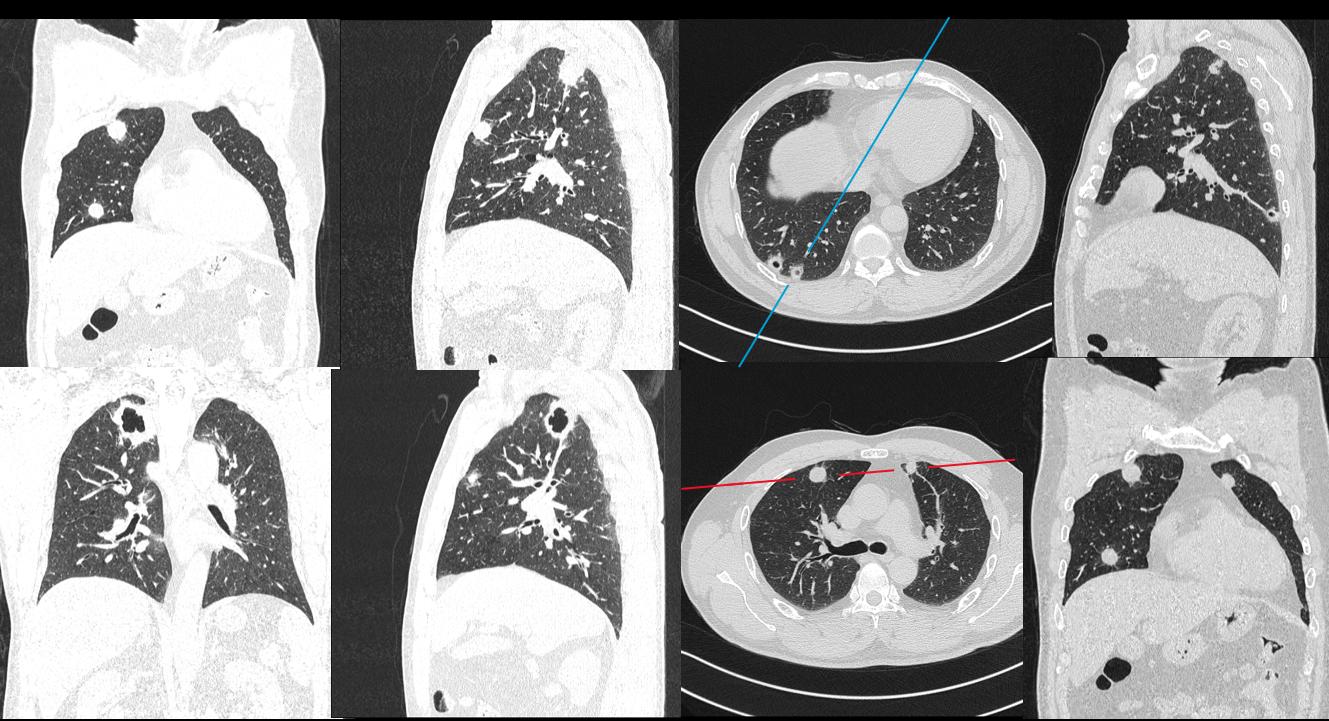

图像:

影像描述:双肺多发结节状密度增高灶,周围可见晕征、毛刺、胸膜牵拉征象,可见空洞样改变,内壁光整,增强轻中度强化,未见淋巴结肿大和胸腔积液。

影像诊断:双肺多发病变(1.真菌感染?2.肺癌?)

病理:肉芽肿性炎。经规范激素+免疫调节治疗后复查,双肺病变明显缩小。

B:影像特点1:双肺多发结节,2部分结节周围可见晕征,3可见空洞,内壁很光整,4未见胸腔积液和淋巴结肿大。空洞的话,中性粒细胞和白细胞不是很高,不考虑金葡菌那种空洞。空洞内壁光整,其余结节周围有晕征,不考虑肺癌并多发转移。结核的话壁薄,卫星灶啊,好发位置啊,病程相对较长,也不考虑。其实隐球菌是不除外的,当然了,一查血管炎自然肯定考虑韦格纳肉芽肿了。这个人做了鼻窦。